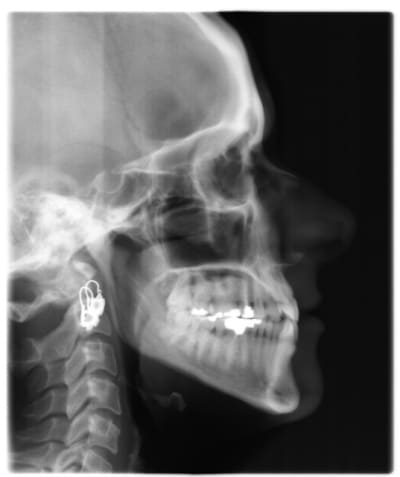

voici de la cas d'un jeune dame de 23 ans qui présente une full classe III subdivision Droite (associée à des compensations incisives de classe III), sur un terrain hyperdivergent. on note un encombrement inferieur d'environ 2 mm et une abrasion des bords triturants des incisives inf (Motif de la consultation)